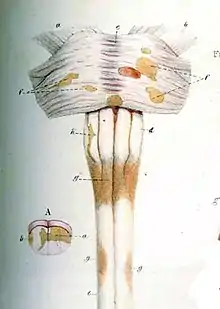

Robert Carswell (1793–1857), a British professor of pathology, and Jean Cruveilhier (1791–1873), a French professor of pathologic anatomy, described and illustrated many of the disease's clinical details, but did not identify it as a separate disease.[189] Specifically, Carswell described the injuries he found as "a remarkable lesion of the spinal cord accompanied with atrophy".[1] Under the microscope, Swiss pathologist Georg Eduard Rindfleisch (1836–1908) noted in 1863 that the inflammation-associated lesions were distributed around blood vessels.[190][191]

The French neurologist Jean-Martin Charcot (1825–1893) was the first person to recognize multiple sclerosis as a distinct disease in 1868.[189] Summarizing previous reports and adding his own clinical and pathological observations, Charcot called the disease sclerose en plaques.

Diagnosis history

The first attempt to establish a set of diagnostic criteria was also due to Charcot in 1868. He published what now is known as the "Charcot Triad", consisting in nystagmus, intention tremor, and telegraphic speech (scanning speech).[192] Charcot also observed cognition changes, describing his patients as having a "marked enfeeblement of the memory" and "conceptions that formed slowly".[25]